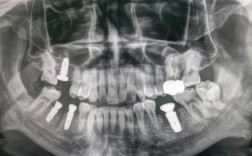

种植牙的放射检查

种植牙需进行放射检查,如CBCT、口腔全景片等,可精准评估牙槽骨条件、邻牙关系及神经位置,为手术方案制定提供依据,保障种植体精准植入...